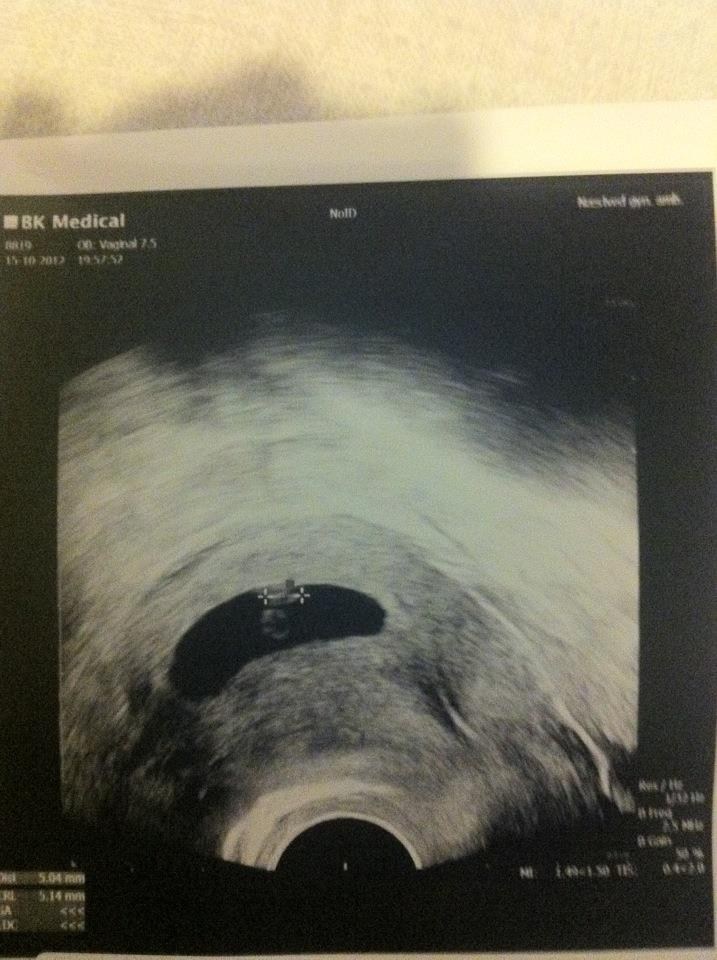

har idag været til scanning oog vi så det fineste hjerteblink :')

den er 5mm og havde en fiiin madpakke, og hule :')